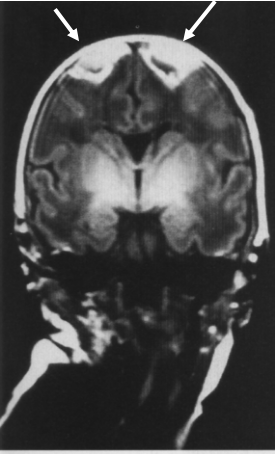

脑血供“分水岭”部位与矢状旁区损伤

足月儿损伤部位

△ 大脑皮层

足月儿脑损伤